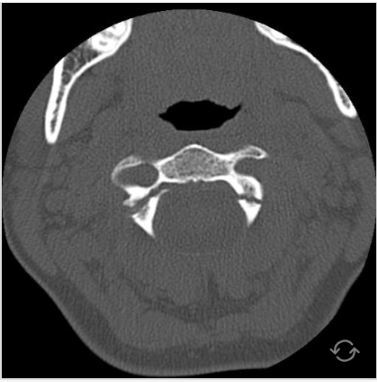

Q

what is this and what is it called?

A

burst # of the atlas

Jefferson #